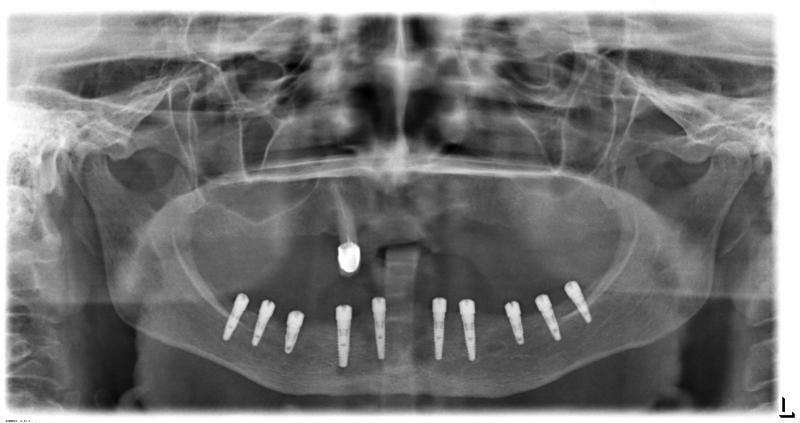

Фото →Установка 10 имплантантов на беззубую челюсть с помощью компьютерной программы: Через месяц после удаления